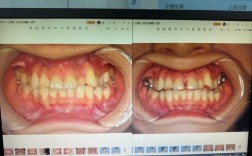

牙齿排列不齐(如拥挤、错位、深覆合等)会导致清洁困难,食物残渣容易嵌塞,进而引发龋齿、牙周炎等问题,长期咬合异常还可能加重牙齿磨损,甚至导致颞下颌关节紊乱(表现为张口弹响、疼痛、咀嚼受限),通过矫正调整牙齿位置,能够消除清洁死角,降低龋齿和牙周病的发生风险,改善咬合功能,保护牙周组织和颞下颌关节健康。

牙齿是面部美学的重要组成部分,排列整齐、形态自然的牙齿能显著改善笑容美观度,甚至对侧貌轮廓有优化作用(如改善“凸嘴”、“地包天”等问题),成年人对社交形象和自我表达的需求更高,矫正后的牙齿美观度提升,往往能直接增强自信心,改善生活质量。